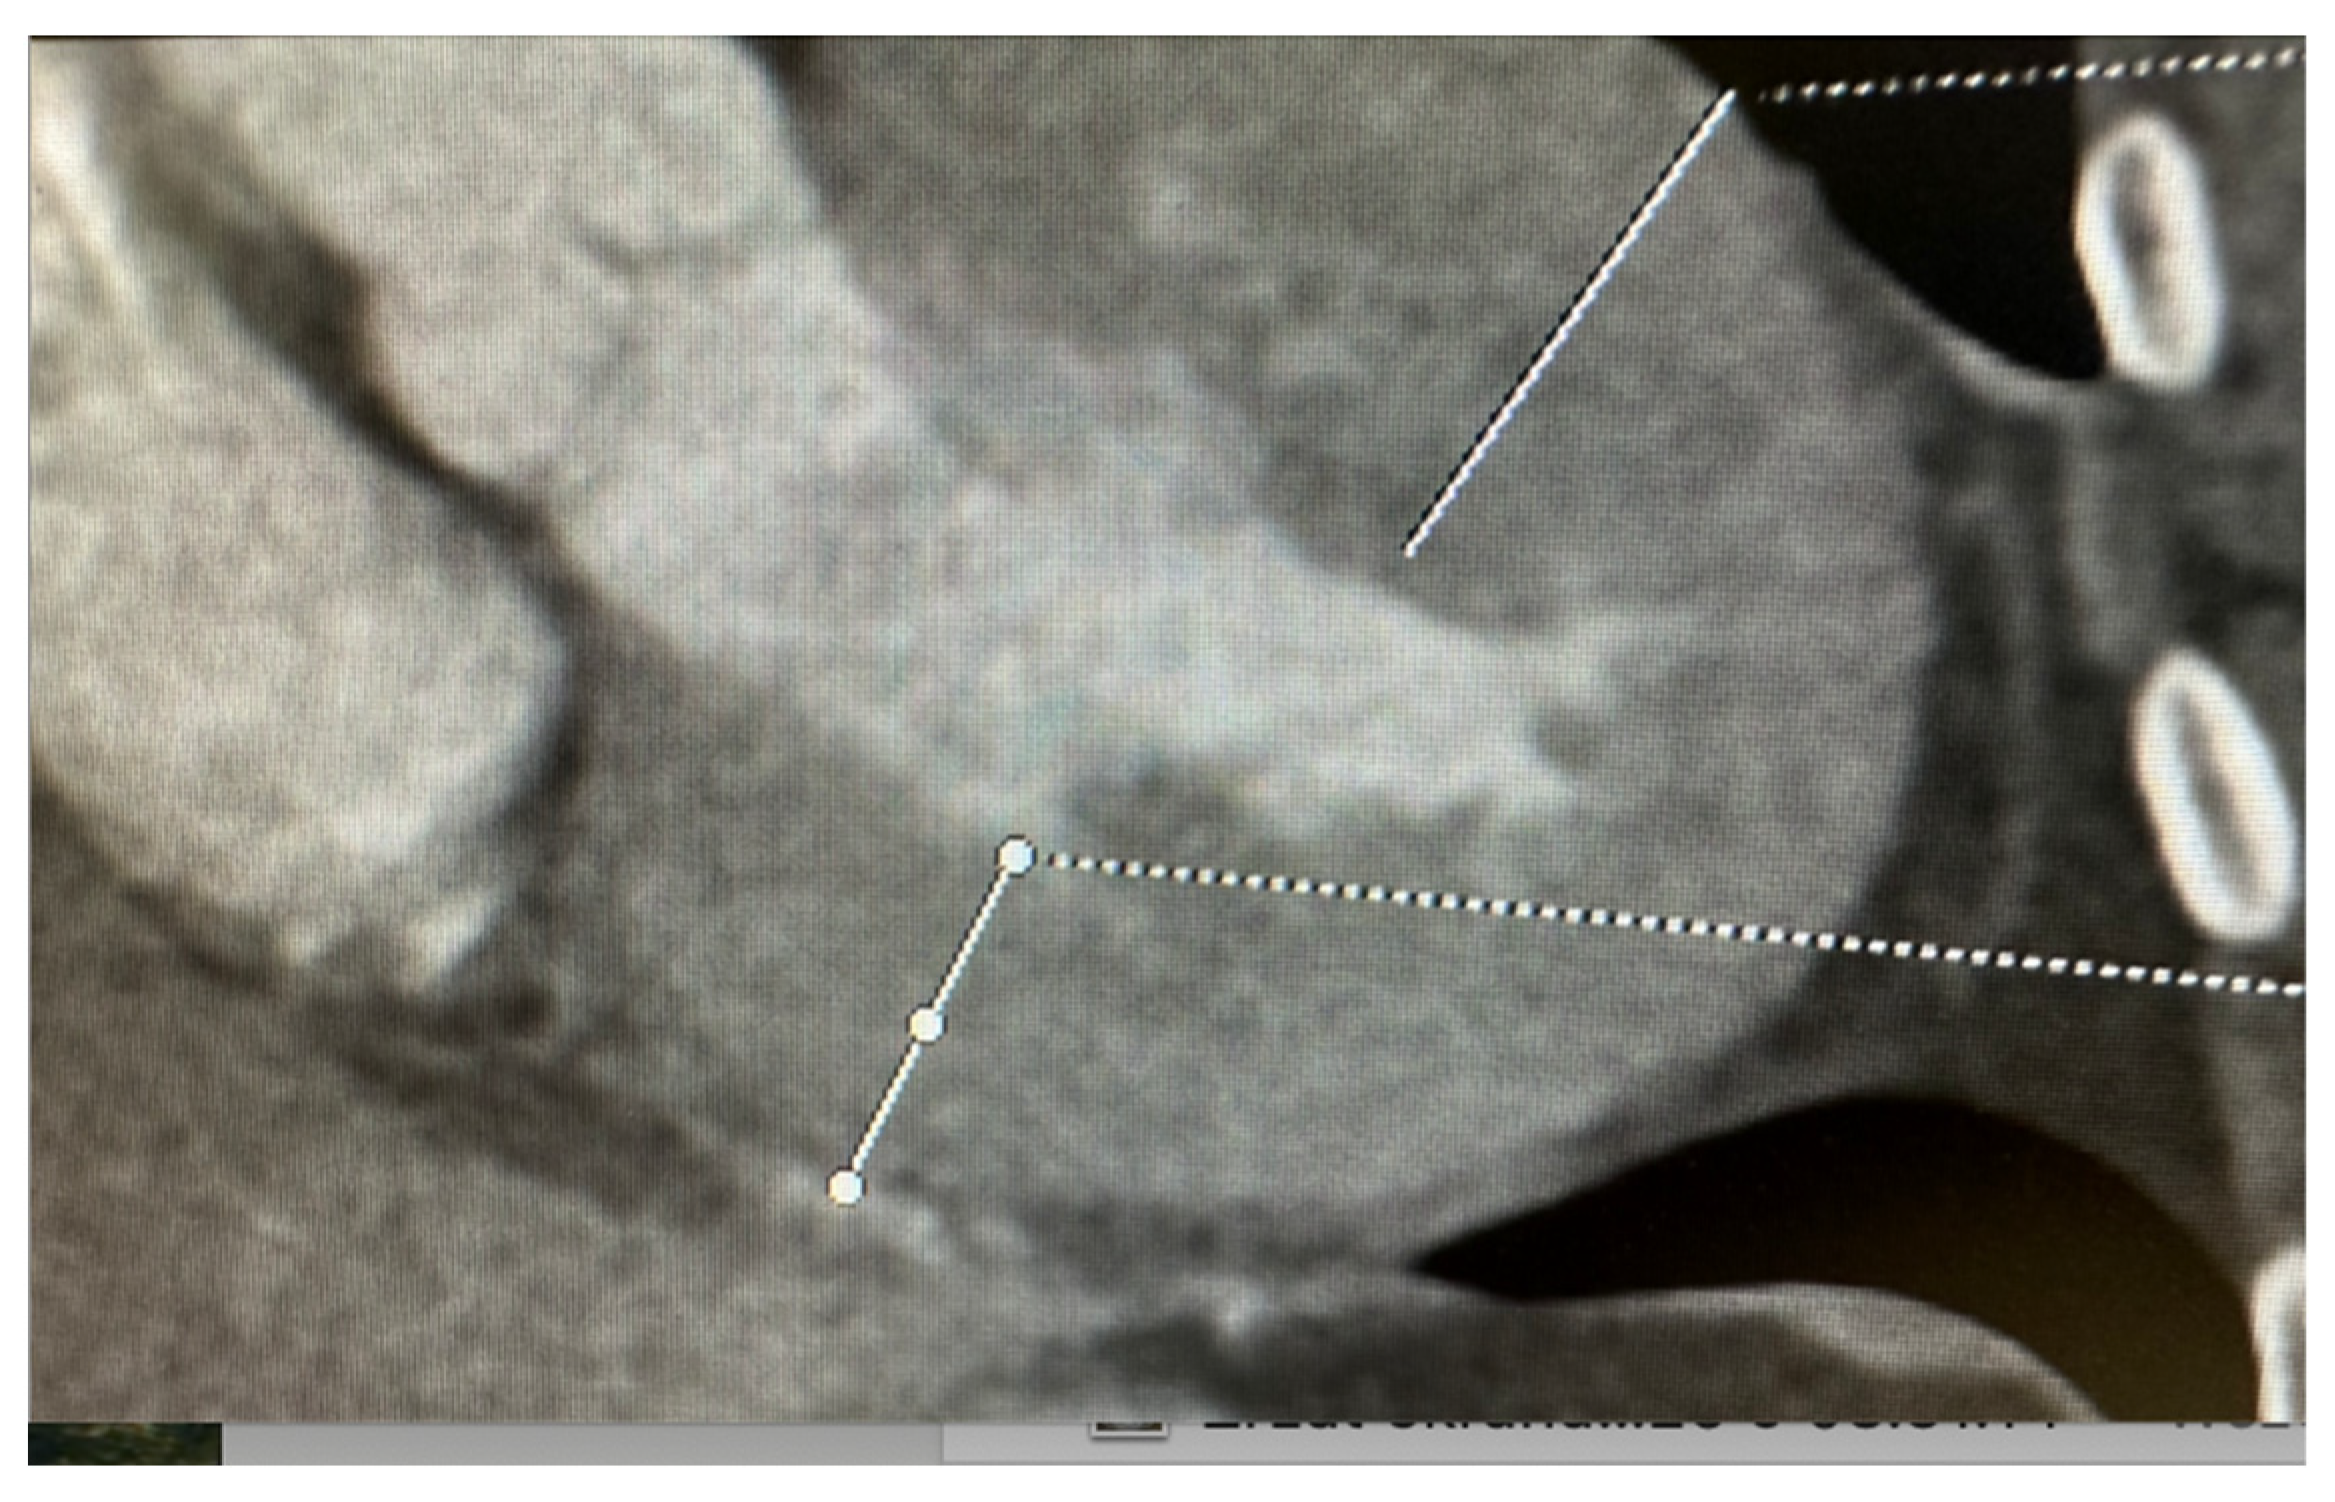

2.3. Computed Tomography: A Complementary Modality

- Choi, A.D.; Thomas, D.M.; Lee, J.; Abbara, S.; Cury, R.C.; Leipsic, J.A.; Maroules, C.; Nagpal, P.; Steigner, M.L.; Wang, D.D.; et al. 2020 SCCT Guideline for Training Cardiology and Radiology Trainees as Independent Practitioners (Level II) and Advanced Practitioners (Level III) in Cardiovascular Computed Tomography: A Statement from the Society of Cardiovascular Computed Tomography. J. Cardiovasc. Comput. Tomogr. 2021, 15, 2–15. [Google Scholar] [CrossRef]

- Pontone, G.; Rossi, A.; Guglielmo, M.; Dweck, M.R.; Gaemperli, O.; Nieman, K.; Pugliese, F.; Maurovich-Horvat, P.; Gimelli, A.; Cosyns, B.; et al. Clinical Applications of Cardiac Computed Tomography: A Consensus Paper of the European Association of Cardiovascular Imaging—Part I. Eur. Heart J. Cardiovasc. Imaging 2022, 23, 299–314. [Google Scholar] [CrossRef]